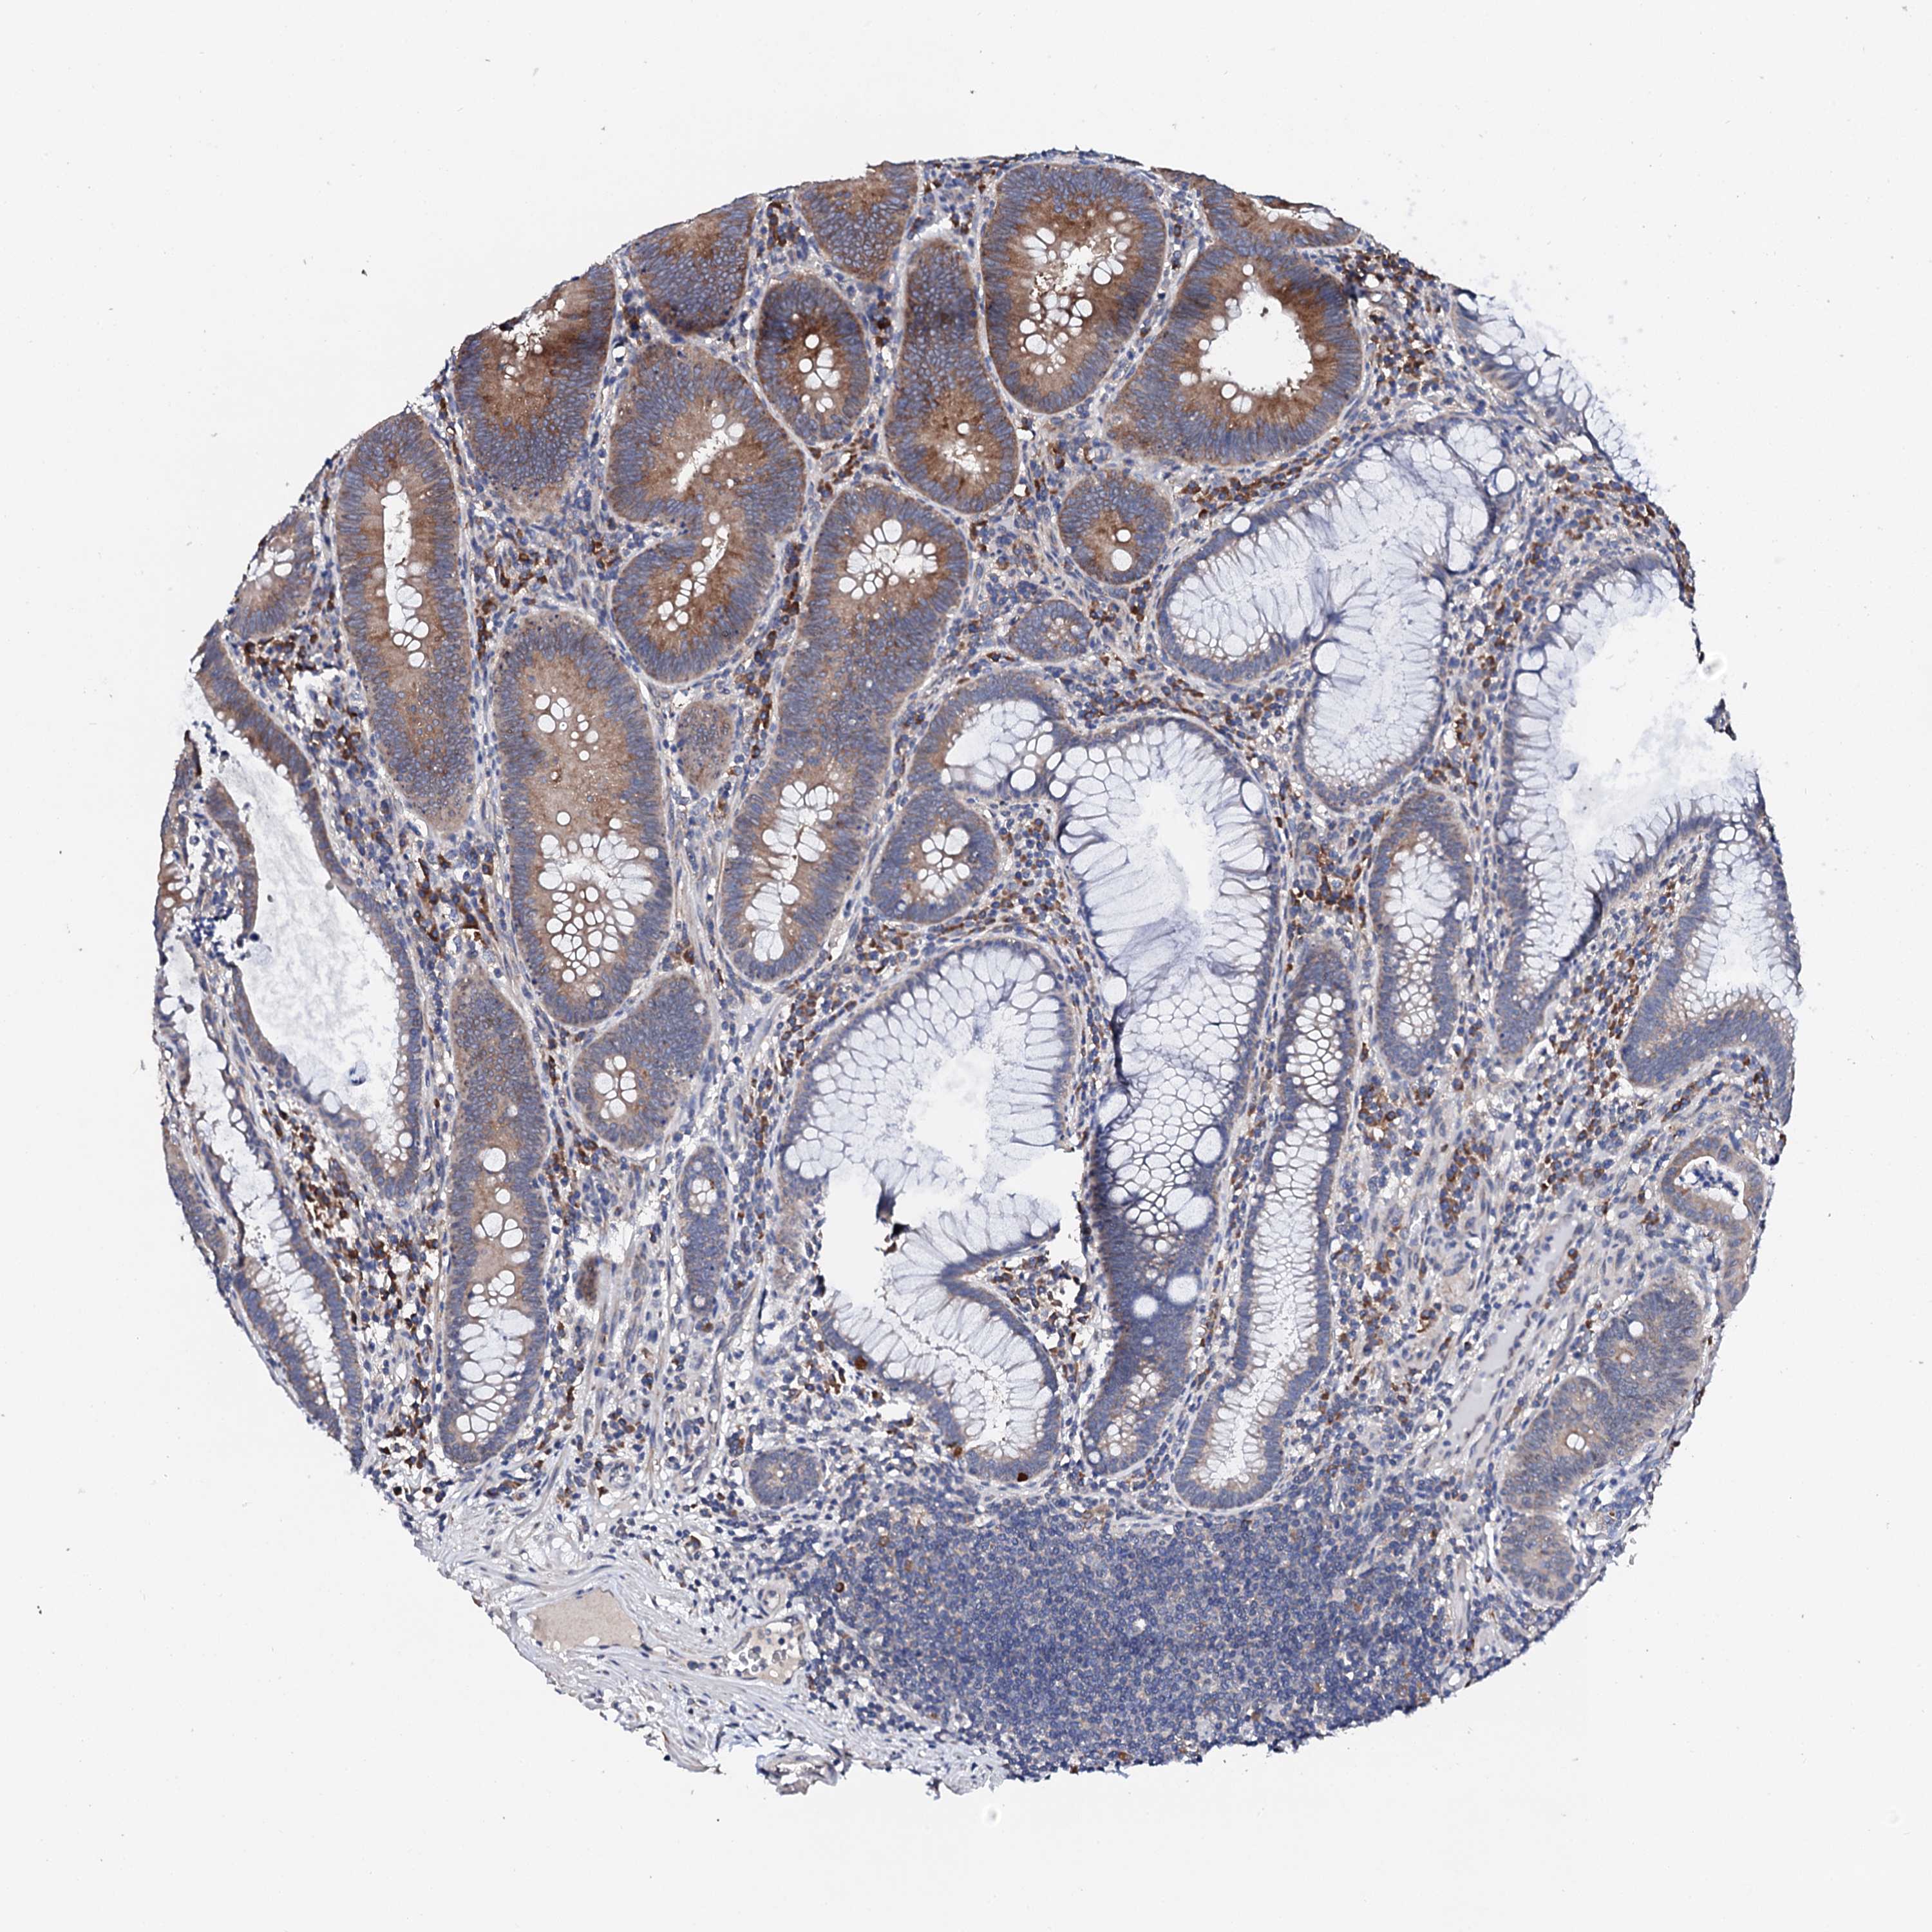

CANCER COLORECTAL CANCER Show tissue menu

Colorectal cancer

Human cancer

Colon adenocarcinoma